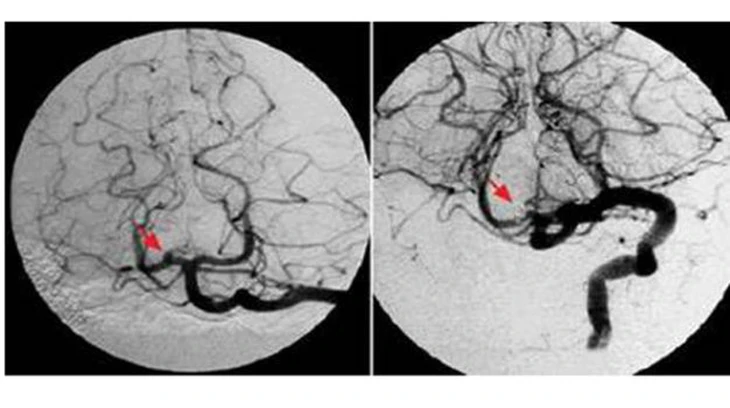

Tại bệnh viện, bước đầu tiên để loại trừ các bệnh lý khác là chụp phim sọ não, bao gồm chụp CT hoặc cộng hưởng từ nhằm kiểm tra tình trạng tụ máu hay xuất huyết.

Đối với các ca bệnh có nhiều yếu tố nghi ngờ, người bệnh sẽ tiếp tục được thực hiện các phương pháp chẩn đoán chuyên sâu để truy tìm triệt để các bất thường trong cơ thể.